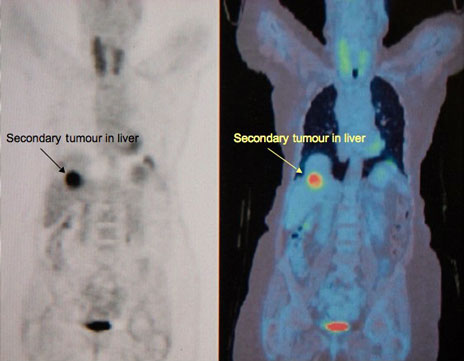

FDG PET scan picture showing a secondary tumour deposit in the liverWhy do secondary tumours develop in the liver?

A cancerous tumour in any part of the body can release cells that go floating in the bloodstream. These cells can land up in another part of the body (such as the liver), and grow there to form secondary cancers, or metastases. The liver is a common site of secondary cancer.

Diagnosis is usually made on the basis of an ultrasound scan, and then a CT or an MR is done to confirm that. Patients who have already undergone surgery for colorectal cancer are often kept on regular surveillance with ultrasound scans, and many liver metastases now get picked up on such scans, at an early stage. A whole body scan called FDG PET is useful in determining if there are other secondaries elsewhere in the body. A radioisotope-labelled substance called Fluoro-deoxy-glucose is injected into the bloodstream, and gets taken up cancer deposits wherever they are. These then show up on a whole-body scan (but only if they are close to 1 cm in size). Colorectal cancers often release a substance in the blood stream, called Carcinoembryonic antigen (CEA). This is known as a tumour marker. If the CEA level in the blood is raised, it very strongly suggests that the patient has colorectal cancer. But the converse does not always apply – if the CEA levels are normal, that does not rule out cancer. Needle biopsy of liver metastases can be done, but it does carry a small amount of risk, and should therefore be restricted to situations where it is absolutely necessary.